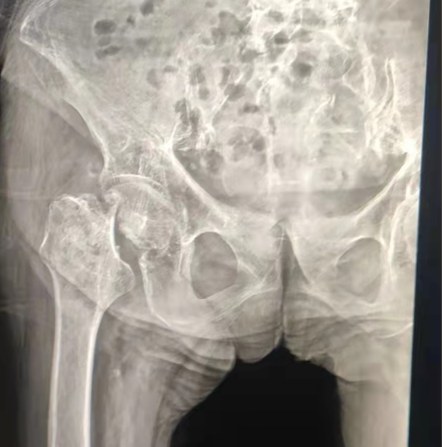

Caso compartido | Un paciente de 70 años de edad, recibió el reemplazo total de cadera con sistema de cadera cementado Lepu

Sistema cementado de la cadera: